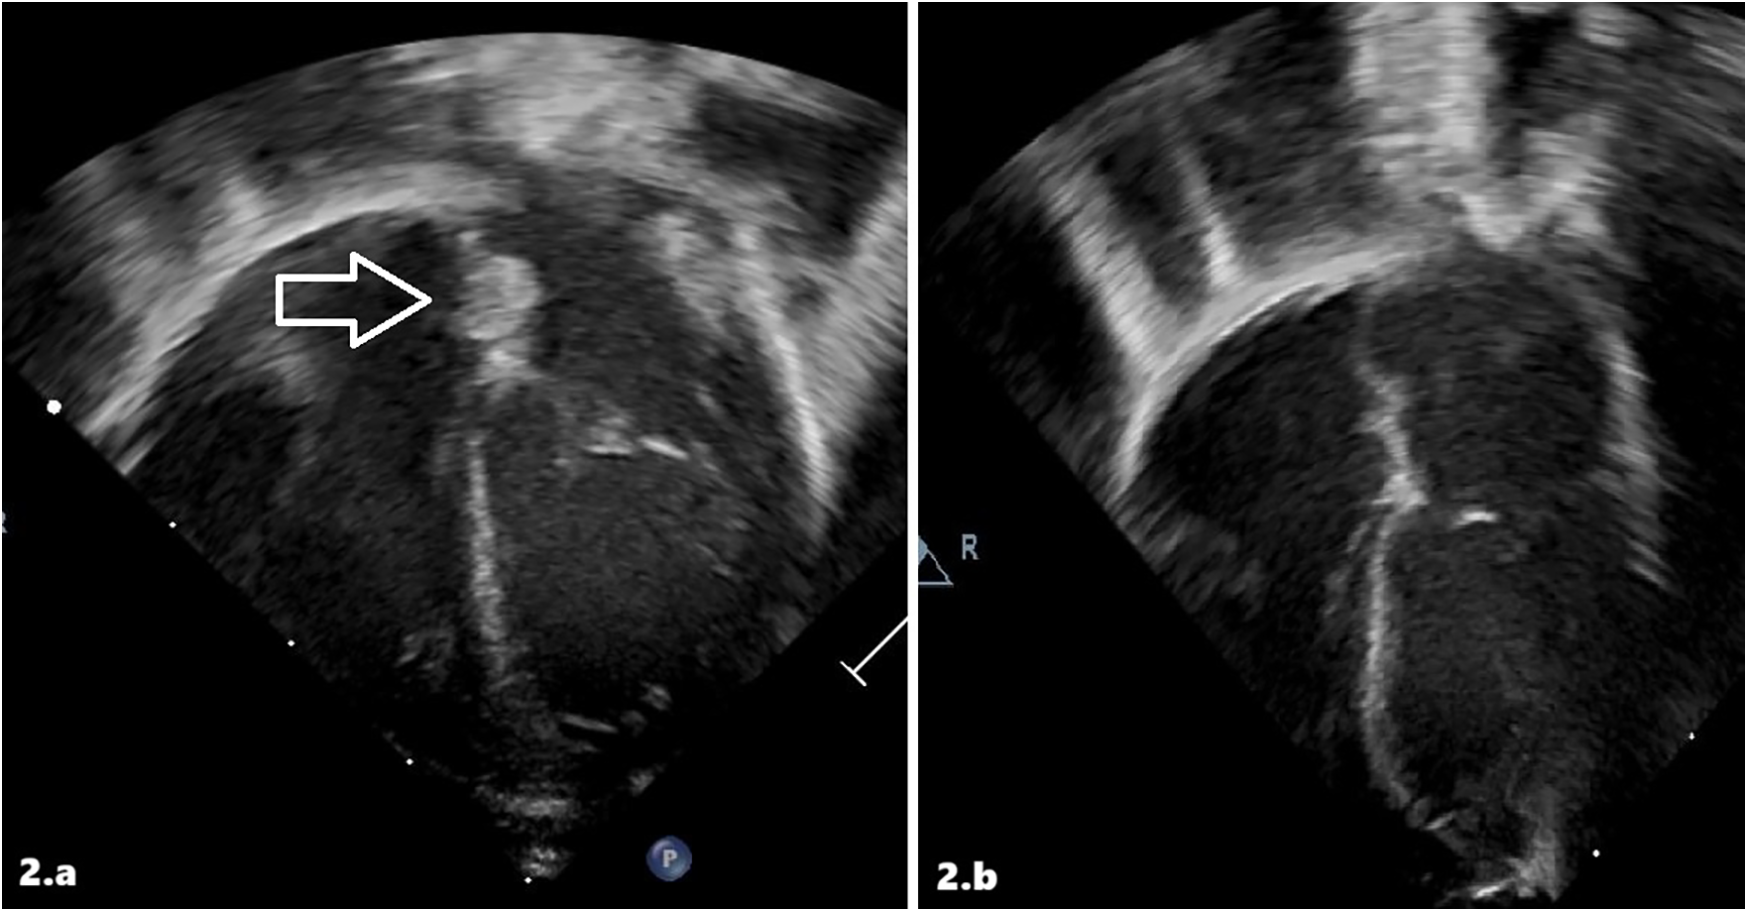

On the 7th day of life, cardiac ultrasound detected a mobile, pedunculated mass in the left atrium attached to the left atrial septum with a maximum diameter of 0.37 × 0.65 cm (Figure 2a). Findings were compatible with the diagnosis of atrial thrombosis, and the newborn was transferred to our III-level NICU. Upon admission to the other hospital, the echocardiographic diagnosis was confirmed. Anticoagulant therapy with LMWH (enoxaparin 170 U/kg twice a day subcutaneously) was started with hematologic monitoring of anti-Xa levels. Abdominal ultrasound was normal. Cerebral ultrasound showed areas of mildly increased echogenicity in deep periventricular white matter, but no evidence of thrombosis. Thrombophilia screening revealed a homozygous mutation in the MTHFR gene (C677 T variant), with normal homocysteine levels. Haematological workup included protein C, protein S, and antithrombin III. On 12th DOL, cardiac angio-CT and echocardiography showed no evidence of intracavitary cardiac mass (Figure 2b). On the 16th day of life, the infant was discharged home with enoxaparin only once/day and then discontinued after a month. We have no data about long-term follow-up.

Figure 2

Intracardiac thrombus at diagnosis (a) and after treatment (b) in patient 2 at echocardiographic scans.